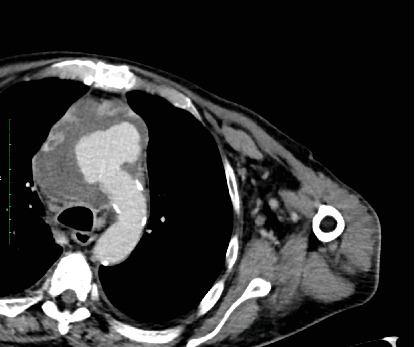

An infection and aortic arch pseudoaneurysm can be fatal if not emergently and adequately treated. Optimal surgical procedures and optimal graft materials remain controversial. We describe a 61-year-old patient who underwent in situ repair of the infected pseudoaneurysm of the aortic arch. A porcine pericardium patch (BioIntegral Surgical Inc., Mississauga, ON, Canada) was used to reconstruct the aortic wall, followed by the reconstruction of the brachiocephalic trunk using a surgeon-made tube. The patient made a full recovery. Self-made tube grafts for in situ reconstruction offer many advantages and may be a valuable option.

Abstract Image